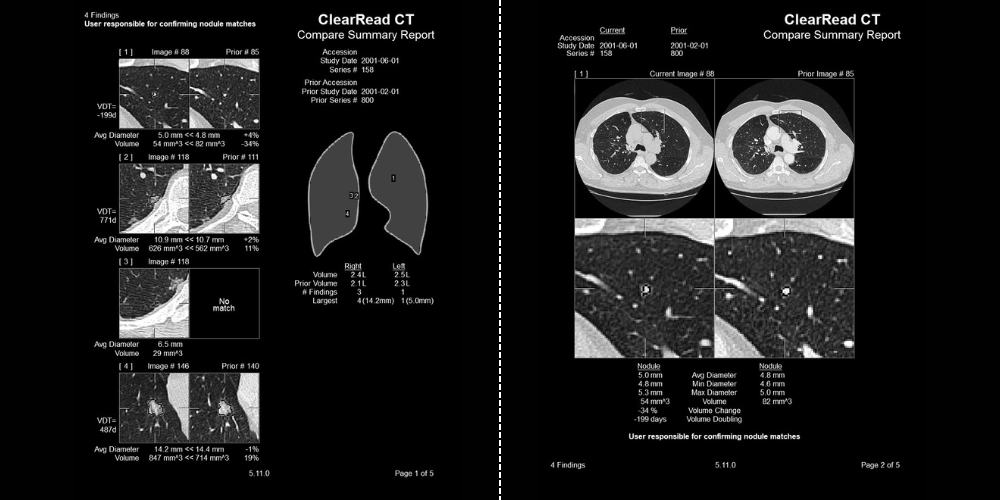

Pulmonary Nodules Automated nodule analysis, current and prior, and reporting to lighten cognitive load

- Fully-automatic nodule detection and analysis

- Quickly & easily compare nodule findings with prior exams – monitor changes in volume, diameter, and doubling time